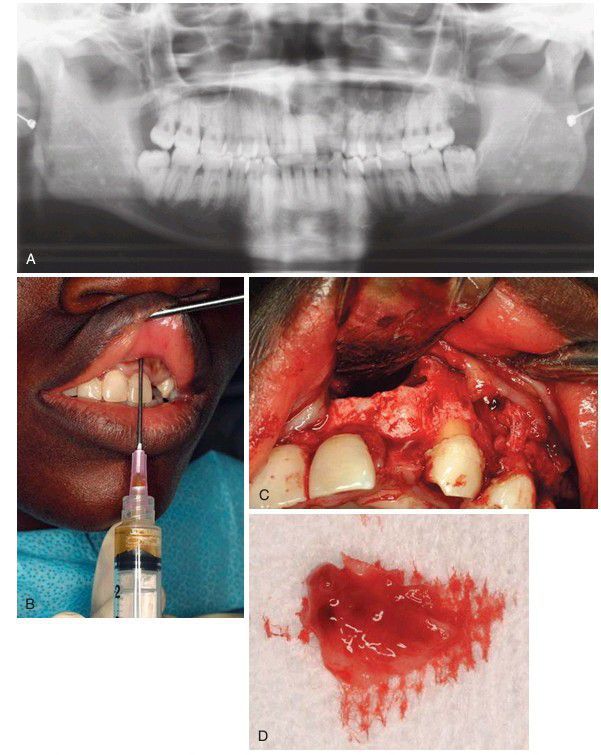

(A) Panoramic radiograph showing a large radiolucency in the left maxilla. (B) Aspiration of a lesion by passing a needle through the mucosa and thin bone over the lesion, revealing straw-colored fluid. (C) After raising a soft tissue flap and removal of bone in the area of the lesion. (D) Removal of a specimen for pathologic examination.